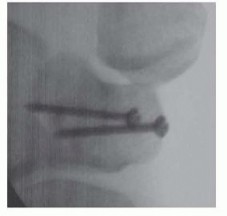

Clinical & Radiographic Imaging Archive